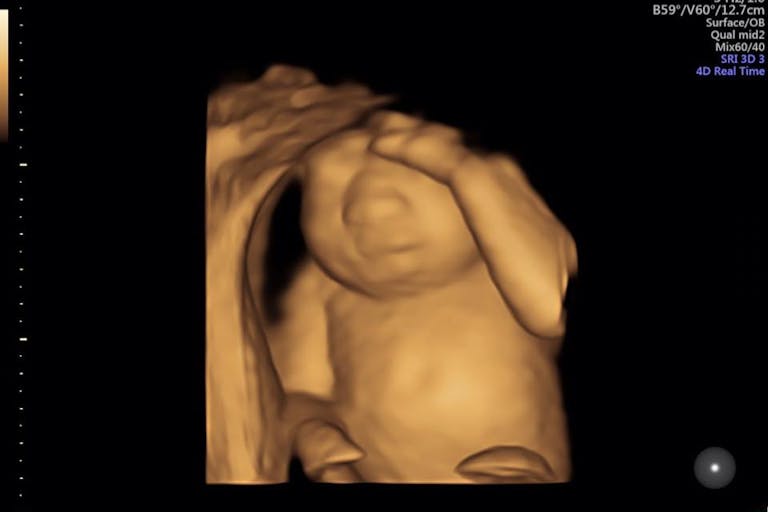

Husband, father, and ESPN writer Royce Young recently posted a photo of his pregnant wife, Keri, on Facebook that has been shared over 12,000 times. In the photo, Keri Young is simply sleeping on the couch, but what her husband has to say about her depicts a woman of incredible strength during her most difficult time in life.

At 19 weeks gestation, the couple learned that their second child, a baby girl, has anencephaly, a condition in which the skull and brain don’t properly grow. Children with anencephaly usually live for only a few minutes, hours, or sometimes days after birth. (Angela is an unusual exception.) The Youngs were devastated, but Royce said that within moments of the diagnosis, his wife was already thinking about everyone except herself.

Knowing that their baby girl is her own person, the couple had her dedicated at church on Sanctity of Human Life Sunday. She is due to be born in early May, and her mother is fearful of that day. For now, though, she is enjoying each kick and private moment with Eva and is happy that this precious little daughter is still growing and living inside of her. The Houston Chronicle featured the Youngs’ story on February 22, helping to spread the word both of life inside the womb and of life that organ donation can give.